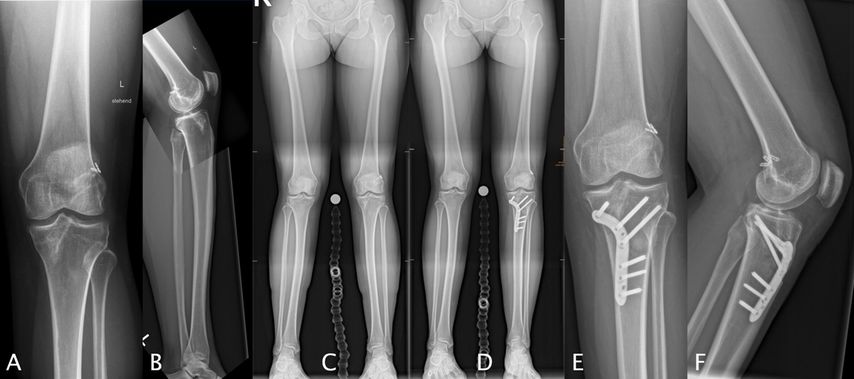

Abb. 3: 33-jährige weibliche Patientin mit zweifacher VKB-Reruptur (A) mit einem erhöhten tibialen Slope von 15° (B) und einer Valgusfehlstellung von 3° (C), behandelt mit einer einzeitigen Revision mitipsilateralem Quadricepssehnengraft und einer varisierenden Slope-reduzierenden HTO (D, E, F)